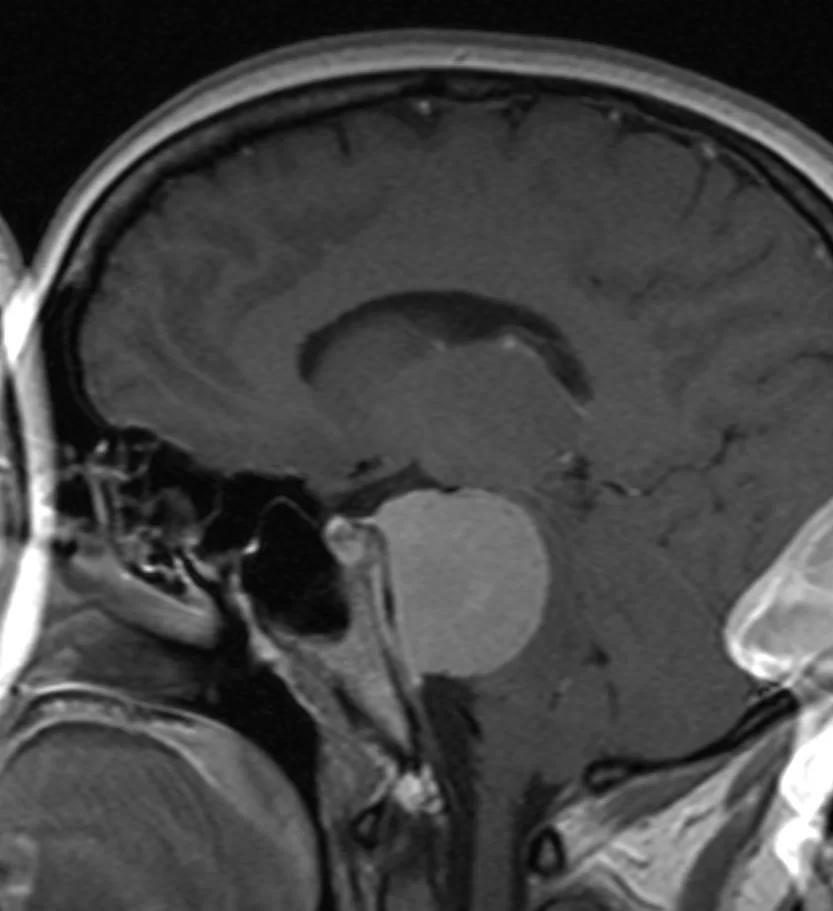

Ο απεικονιστικός έλεγχος με μαγνητική τομογραφία ανέδειξε ευμεγέθη όγκο με επέκταση τόσο στον μέσο όσο και στον οπίσθιο κρανιακό βόθρο και σημαντική πίεση επί του στελέχους, συμβατό με μηνιγγίωμα του λιθοειδούς-αποκλίματος.

Διενεργήθη συνδυασμένη υποκροτάφιος – προσιγμοειδική προσπέλαση.

Η μετεγχειρητική αξονική τομογραφία εγκεφάλου δείχνει σημαντική μείωση του όγκου, με ελάχιστα υπολειμματικά στοιχεία στην περιοχή του σηραγγώδους κόλπου δεξιά. Η ιστολογική εξέταση ανέδειξε μηνιγγίωμα (WHO I).